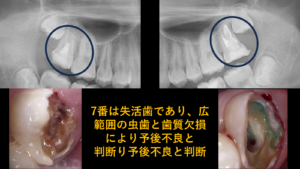

課題2: 7番(第二大臼歯)が失活歯(神経がない歯)で、将来的な破折や再感染のリスクが高い

それは、奥から2番目の歯(7番:第二大臼歯)の状態が非常に悪かった(失活歯)ことです。